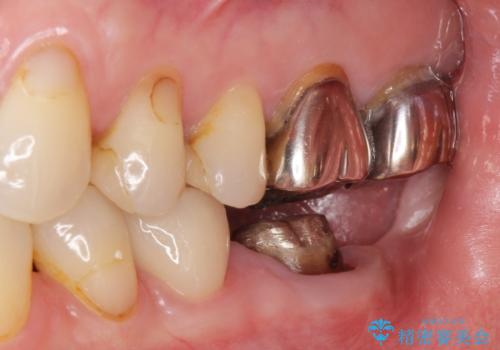

- 銀歯のやりかえ希望の患者様です。

症状もなく、レントゲンでも根尖病巣が見られないため

患者様と話し合った結果、中の土台は外さず、被せ物のみのやりかえとなりました。